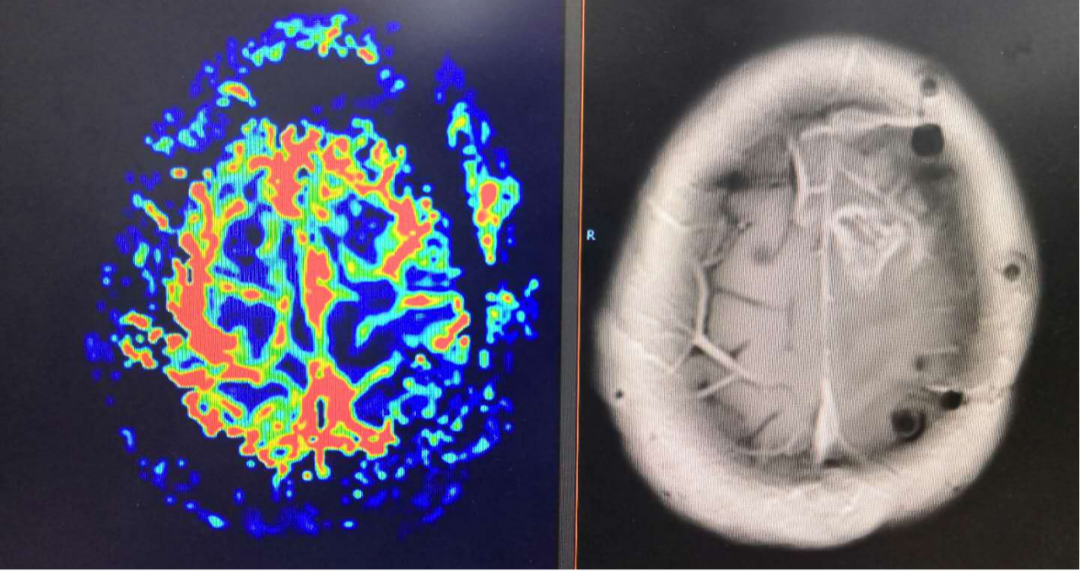

复查MRI提示:局部病灶强化,PWI提示局部灌注有缺失,考虑病情进展,同时不除外假性进展,患者脑水肿范围较大。

根据以往经验调整治疗方案:1、根据复发胶质瘤相关指南,首选抗血管生成药治疗;2、MDT讨论:病灶累积胼胝体,再次手术难度大;3、给予“阿帕替尼425mg qd po”。之后显示水肿变小,灌注降低。继续原方案治疗。